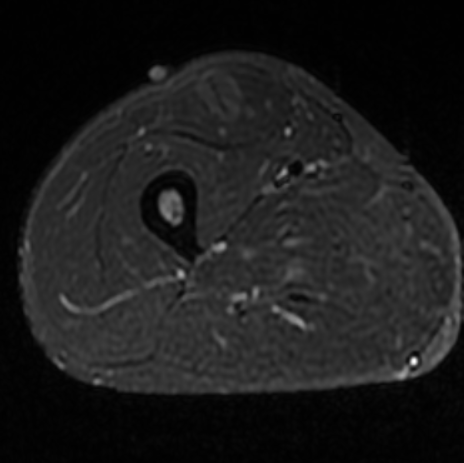

Показания для проведения МРТ мягких тканей:

- боль в мягких тканях;

- травма;

- подозрение на абсцесс или опухоль;

- оценка состояния мягких тканей после операции;

- увеличение и болезненность лимфатических узлов.

Как проводится МРТ мягких тканей?

Перед укладкой в томограф необходимо снять все металлические предметы.

После этого пациент ложится на стол сканера, который постепенно перемещается в аппарат. Во время сканирования следует лежать неподвижно, чтобы получаемые изображения были четкими и неискаженными.

Исследование длится 40 минут.

Результаты исследования обычно готовы в течение дня, но при острой патологии они могут быть предоставлены сразу.

После исследования вы получаете:

- высококачественные снимки органов и тканей;

- подробную расшифровку результатов;

- возможность детального разбора с участием врачебного консилиума.